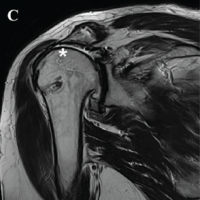

Based on these observations, the case was classified as Crowe grade 3 osteoarthritis. Due to the severe high dislocation of the femoral head and joint contracture, anatomical reduction of the hip joint was considered infeasible. In addition, the extent of posterior and superior bone defects precluded secure fixation using a press-fit cementless cup. Therefore, the use of a reinforcement ring was deemed necessary, and the GAP II ring was selected for its capacity to accommodate multiple screw fixations and flexible hook bending. The procedure was performed through the ALS approach. Due to excessive anterior wall coverage, removal of the femoral head necessitated partial excision of the anterior wall. Osteophytes that could cause joint impingement were also removed (Fig. 3).